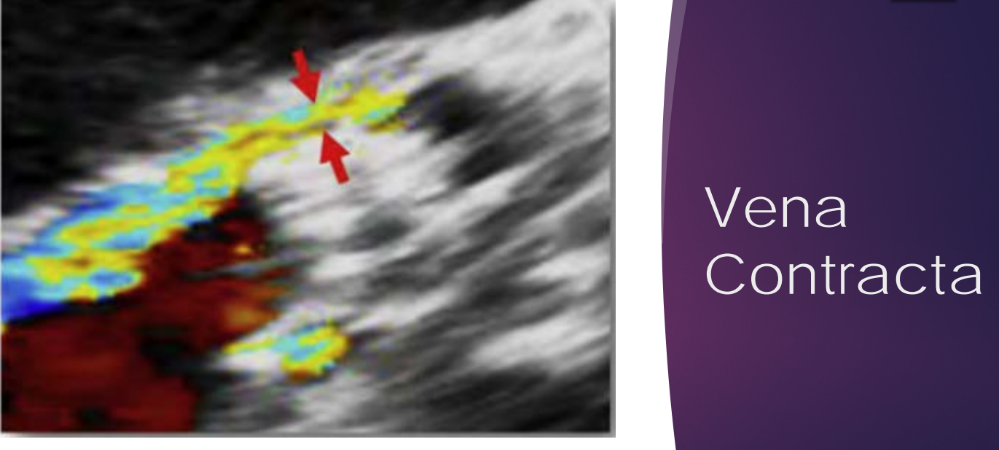

Color Doppler evaluation of the AR.

what measurement/things you need to do (3 things to name )

Flow convergence, VC, and proximal jet extension into the LVOT and left ventricle

Prosthetic Aortic Valves

Limitations of Flow convergence, VC, and proximal jet extension into the LVOT and left ventricle method include what (two things)

Limitations of this method include reverberation and shadowing from the prosthesis

The VC width, area, and circumferential extent could be assessed from a carefully obtained what view?

The VC width, area, and circumferential extent could be assessed from a carefully obtained short-axis view

Measuring the width of an what jet in the what view may overestimate or underestimate ? - which one? regurgitation severity

Measuring the width of an eccentric jet in the outflow tract may overestimate

regurgitation severity

Wall-impinging aortic paravalvular jet may lead to over or underestimation because why?

Wall-impinging aortic paravalvular jet may lead to underestimation because of an unimpressive color Doppler jet area